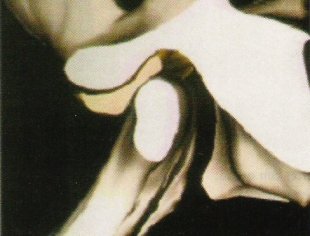

De ésto nos van a informar en radiología al realizar una RMN de ATMs. Esta prueba se muestra especialmente útil y superior a los restantes métodos de diagnóstico por imagen, en el estudio de la posición del disco articular y de sus anomalías de posición (desplazamientos discales) y estructurales. En condiciones normales, cuando se explora la ATM en boca cerrada y en cortes sagitales, el disco aparece como una cinta grisácea oscura situado entre el cóndilo y la eminencia temporal; el extremo anterior (banda anterior) se halla en la posición horaria de las 9 mirando a la cima de la eminencia, y el extremo posterior (banda posterior), más grueso, en la posición de las 12 de la cabeza condílea.

La banda posterior en relación con la cabeza condílea es el punto de referencia para apreciar la posición y desplazamiento del disco; así, se considera que hay desplazamiento discal anterior cuando, con la boca cerrada, el disco está por delante de la posición horaria de las 12 con respecto a la cabeza condílea.

La posibilidad de ver el menisco y su comportamiento en situación de boca cerrada y boca abierta nos va a servir de gran ayuda para localizar su posición, ver su forma y sus defectos.